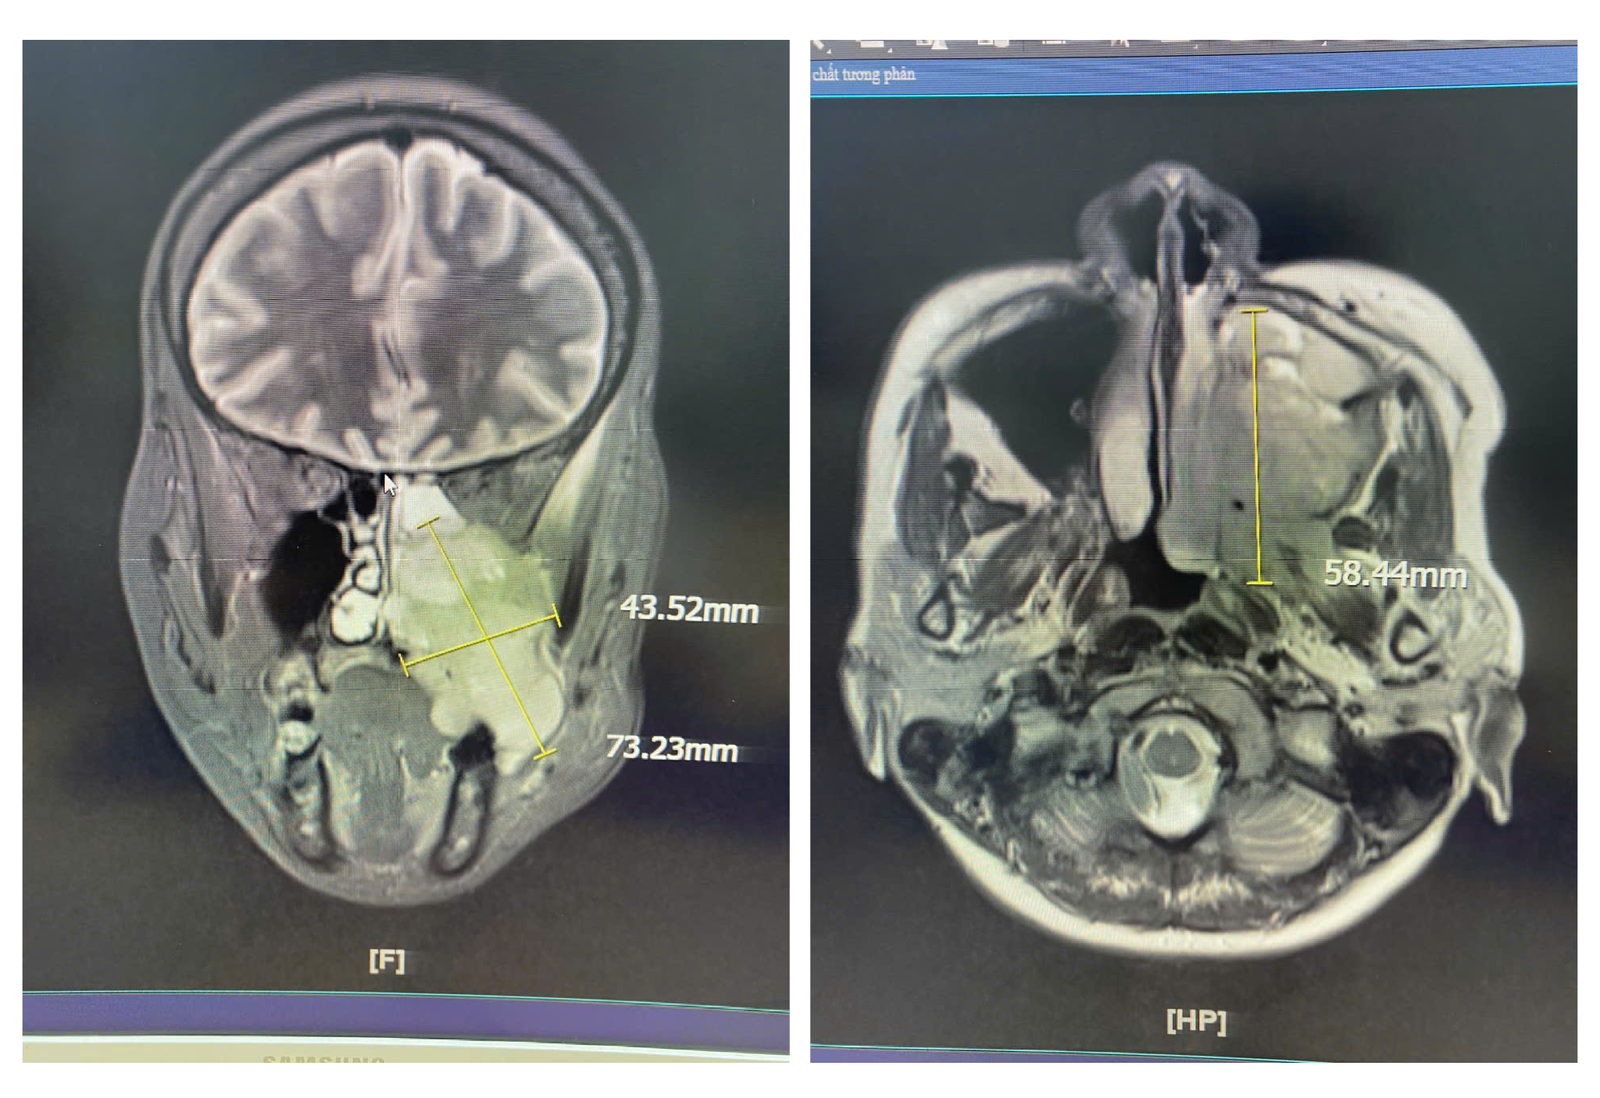

Các chẩn đoán hình ảnh bằng MRI, nội soi tai mũi họng cho thấy chị S. có khối u xuất phát từ xoang hàm - sàng trái, lan xuống khẩu cái, hố chân bướm hàm và vùng dưới thái dương trái. Kết quả sinh thiết mẫu mô từ hốc mũi và răng ghi nhận tổn thương phù hợp với Carcinoma tế bào gai không sừng hoá (ung thư).

Khối u với kích thước lớn có thể nhận thấy dễ dàng trên phim chụp cộng hưởng từ MRI (Ảnh: Bệnh viện cung cấp)

Giải thích kết quả này, ThS.BS.CKII Lê Nhật Vinh - Phụ trách khoa Liên chuyên khoa, Bệnh viện Đa khoa Quốc tế Nam Sài Gòn cho biết: Khối u không còn nằm giới hạn trong xoang mũi, mà đã lan sâu đến nhiều khu vực giải phẫu quan trọng như khẩu cái (trần miệng), vùng sàn sọ và hố chân bướm hàm.